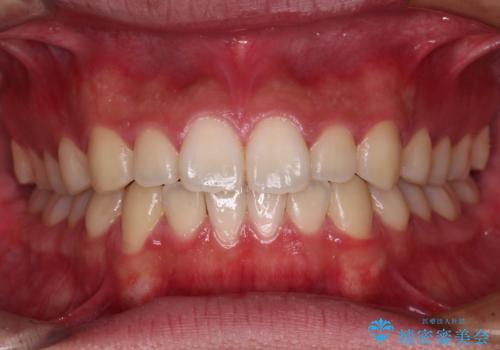

マウスピース矯正は毎日しっかりと装着することがとても大切です。

こちらの方はしっかりと指示を守って装着してくださったため、予定通り治療を終えることができました。